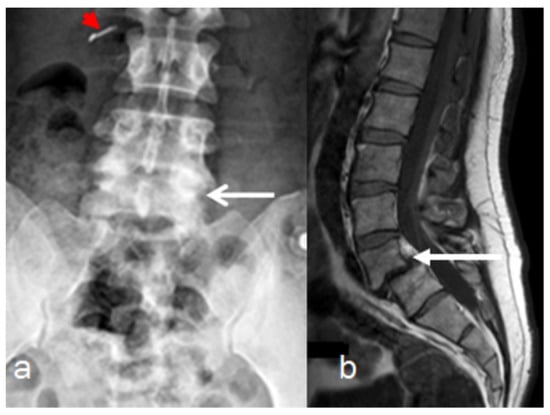

Reformatted CT scan of the craniocervcial and the cervical vertebrae of the proband showed odontoid hypoplasia secondary to neurocentral synchodrosis and defective formation of the cervical vertebrae in connection with synchondrosis. The latter is the development of union between two bones by the formation of either hyaline cartilage of fibrocartilage. A synchondrosis is usually temporary and exists during the growing phase until the intervening cartilage becomes progressively thinner during skeletal maturation and is ultimately obliterated and converted into bone before adult life. In other words, a synchondrosis is a cartilaginous joint. It allows only slight movement between bones compared to the synovial joint, which has a much greater range of movement. The process of ossification within the centrum of the vertebral body is similar to that of tertiary ossification. Longitudinal growth mostly occurs at the chondro-epiphyseal portions of the end-plates. In this patient, it was obvious that synchondrosis was a permanent rather than a temporary process. Reformatted Coronal CT scan of the cervical spine showed butterfly vertebrae (defective formation), note the detached cephalic part of the odontoid process (arrowhead) in connection with extensive cervical spine synchondrosis causing the mal-development of butterfly vertebrae (Figure 1a). Reconstruction CT scan of the cervical spine showed atlanto-axial dislocation (arrows). Both parents experienced low backpain since their late adolescence (spondylolisthesis was the diagnosis). AP radiograph of the lumbar vertebrae at the age of 32-year-old mother showed osteoarthritis of the facet joints of L5 (arrow) associated with diminution of the heights of L4/5. Note the increased level of calcification that signifies facet arthritis. Surprisingly, the AP pelvis radiograph of the mother at age of 32 years showed incidental diagnosis of ossification of the abdominal aorta. The mother is asymptomatic, but such finding is of utmost importance. Ossification of the abdominal aorta signifies a state of subclinical atherosclerosis with subsequent vascular hazards-red arrowhead (Figure 2a). Sagittal spine MRI of the 38-year-old father showed dysplastic spondylolisthesis of L4/5 (arrow) that might leads to spinal stenosis (Figure 2b). Phenotype/genotype of the family with spondylo-meg-epiphyseal-dysplasia appears in Table 1.

Figure 2. (a,b). Imaging of the parents, AP radiograph of the lumbar vertebrae of the 32-years-old-mother showed osteoarthritis of the facet joints of L5 (arrow) associated with diminution of the heights of L4/5. Note the increased level of calcification that signifies facet arthritis. Surprisingly, incidental diagnosis of early ossification of the abdominal aorta-red arrow head (a). Sagittal spine MRI of the 38-year-old father showed dysplastic spondylolisthesis of L4/5 (arrow) that might leads to spinal stenosis (b).